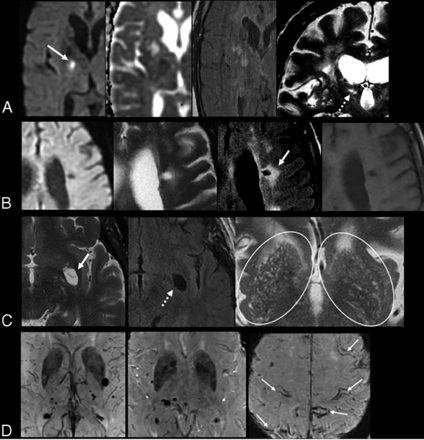

According to the STRIVE criteria, the term “recent small subcortical infarcts” refers to a recent infarct occurring in the territory of a perforating arteriole with symptoms or imaging features that suggest a timeline of a previous few weeks. However, in most patients, these lesions can appear without apparent clinical symptoms (silent infarcts) (Online Supplemental Data).11 The term “recent” is preferred instead of “acute” because it includes both the hyperacute stage and the first few weeks of the lesion.11 These lesions typically measure ≤20 mm in their maximum diameter in the axial plane, though in the coronal plane, they can appear slightly larger and elongated, reflecting the territory of the occluded perforating arteriole (Fig 2A). They are best identified with hyperintense signal on DWI, hypointense signal on an ADC map, and hyperintense signal on T2-weighted and FLAIR sequences. The most common fate of these lesions on long-term follow-up is cavitation to become a lacune (in 28%–94%, depending on the duration of follow-up), turning into a nonspecific focus of T2/FLAIR hyperintensity, or eventually completely disappearing.2,8 Furthermore, STRIVE proposes that lesions in the basal ganglia and internal capsule of >20 mm are a different subtype and, therefore, should be classified as striatocapsular infarcts instead of small subcortical infarcts. Similarly, infarcts of the anterior choroidal artery are etiologically and anatomically distinct.

A, Recent subcortical infarct in the right lentiform nucleus in a 59-year-old woman with a history of hypertension. From left to right, axial DWI, ADC map, FLAIR, and coronal T2WI show restricted diffusion (solid white arrow, A). On coronal T2WI, the elongated morphology of the acute infarct in the craniocaudal axis (dashed white arrow, A) is related to the territory of a perforating artery. B, A lacune of presumed vascular origin in a 67-year-old man with a history of dementia. From left to right, axial DWI, T2WI, FLAIR, and T1WI show a remote lacunar infarct in the left frontal corona radiata, which demonstrates T2 hyperintensity with a peripheral rim of gliosis, best seen on FLAIR image (solid white arrow, B). C, Prominent perivascular spaces in a 63-year-old man with a history of dementia. A prominent perivascular space is noted in the left insular region with a centrally traversing vessel (solid white arrow, C), without peripheral gliosis on the FLAIR image (dashed arrow, C). Additionally, there are >20 dilated perivascular spaces in the bilateral basal ganglia on axial T2WI (circles, C). D, Cerebral microbleeds with cSS in an 87-year-old man with a history of CAA who presented with a worsening mental status. Axial SWI demonstrate multiple foci of susceptibility artifacts predominantly involving the basal ganglia and thalami, consistent with microbleeds. Additional areas of scattered cortical subarachnoid hemorrhagic staining (arrows, D) indicate cortical superficial siderosis.

Lacunes of Presumed Vascular Origin.

The STRIVE guidelines define lacunes of presumed vascular origin as round or ovoid, subcortical, fluid-filled cavities (with signal similar to that of CSF in all sequences), measuring between 3 and 15 mm in diameter, consistent with a previous, small subcortical infarct or hemorrhage located in deep gray and white matter and in a territory of perforating arteriole (Fig 2B and Online Supplemental Data). These lesions typically demonstrate a surrounding gliotic rim of T2 FLAIR hyperintensity (Figs 3 and 4), which can be a useful feature when present. A peripheral gliotic rim can also surround perivascular spaces when they pass through an area of white matter hyperintensity. Although lacunes are commonly seen in older patients without symptoms, they are associated with an increased risk of stroke, dementia, and gait impairment.5,11

Perivascular Spaces, Also Called Virchow-Robin Spaces.

Perivascular spaces are extensions of the extracerebral fluid space that are covered by the pia mater, which surrounds cerebral vessels from the brain surface into and through the brain parenchyma. These are commonly microscopic and not visible on conventional neuroimaging, but when they become prominent and numerous, they are considered a marker of SVD. PVS have been shown to be associated with other SVD markers such as WMH and lacunes, but not atrophy.11 PVS have a signal intensity similar to that of CSF in all sequences and appear round or ovoid with a diameter of <3 mm but can appear more elongated when imaged parallel to the course of the penetrating vessel. They are typically located in the inferior basal ganglia, centrum semiovale, and midbrain and do not have a surrounding gliotic rim (in contrast with lacunes) (Fig 2C and Online Supplemental Data). Although lacunes and PVS can have similar MR imaging features, pathologic studies have demonstrated that lesions that are <3 mm in diameter are more likely to be perivascular spaces than lacunes.11 A traversing vessel can sometimes be seen in the center of a perivascular space when imaged at high resolution, another differentiator of PVS versus lacunes (Fig 2C). The severity of PVS is typically assessed on axial T2-weighted images using a validated 4-point visual rating scale based on the total number of PVS (0 indicating no PVS; 1 [mild], ≤10 PVS; 2 [moderate], 11–20 PVS; 3 [moderate to severe], 21–40 PVS; and 4 [severe], >40 PVS) in the basal ganglia and centrum semiovale (Table 2).33 The topography of PVS can be a helpful characteristic of the underlying SVD type: PVS are likely associated with arteriolosclerosis when located in the basal ganglia, and they are more likely to be related to CAA when located in the centrum semiovale (Fig 4).10 However, the clinical significance of PVS remains unclear; a few studies have reported that PVS can be associated with an increased risk of dementia if located in the basal ganglia and white matter.5,10,36

CMB.

CMB are small round or ovoid lesions (≤10 mm in diameter) of marked hypointensity with associated blooming on T2 gradient-echo (T2*) or other sequences that are sensitive to susceptibility effects, especially SWI (Fig 2D and Online Supplemental Data). CMB correspond to hemosiderin-laden macrophages in perivascular tissue, consistent with vascular leakage of blood cells.5 Several visual scores are available, including the Microbleed Anatomical Rating Scale and the Brain Observer MicroBleed Scales, which have reasonable intrarater and interrater reliability for the presence of definite microbleeds.37,38 In fact, a few recent publications have proposed a novel automatic method to detect CMB from MR images by exploiting the 3D convolutional neural network.39 CMB are associated with an increased risk of cognitive decline and ischemic and hemorrhagic stroke, though the risk of dementia appears higher in patients with CMB restricted to a superficial/lobar location compared with those with deep involvement.5,10 Two other hemorrhagic manifestations of SVD include cSS and spontaneous intracerebral hemorrhage (in contrast to secondary hemorrhage due to other causes such as trauma and vascular malformations).